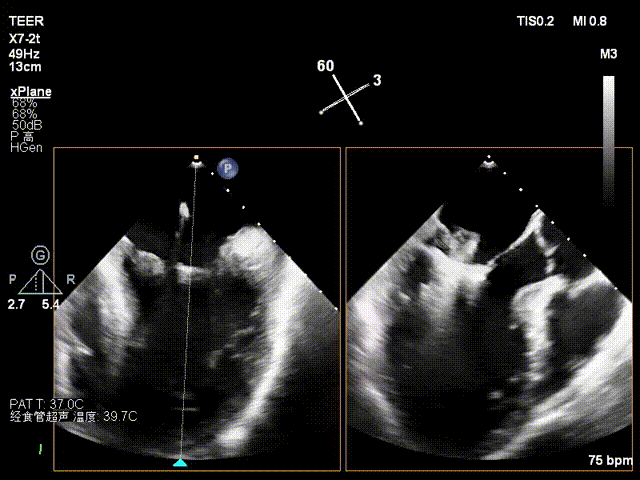

术前潘宏伟教授、何晋教授团队讨论决定,先于2偏1区置入一枚长宽(XW0612)夹解决最大的一处脱垂,再依次向内侧补夹子。术中房间隔穿刺高度:4.4cm,于2偏1区植入一枚长宽(XW0612)夹,夹闭后L侧无残余脱垂。再于M侧2区Side by side植入一枚长宽(XW0612)夹,夹闭后第一枚夹子较前稳定,M侧有残余脱垂。最后于M侧2偏3区植入一枚长窄(XN0412)夹,夹闭后残余功能性反流Trace,压差5mmHg,术毕,反流即刻由术前重度降低为Trace,左房压由术前45mmHg降至术后22mmHg,肺静脉逆流几乎消失,患者明显获益。

房间隔穿刺高度

导引鞘置入

于2偏1区置入一枚长宽夹

瓣叶捕获.

L侧无残余脱垂及反流

于M侧平行置入第二枚长宽夹

瓣叶捕获

Bouncing明显

组织桥稳定

M侧有残余脱垂及反流

于M侧植入一枚长窄夹

夹闭后残余微量功能性反流

3D评估组织桥

TMPG:5mmHg